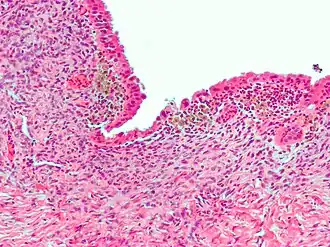

![]() Micrografía que muestra endometriosis (tinción H&E), una causa común de dolor pélvico crónico en las mujeres. | ||